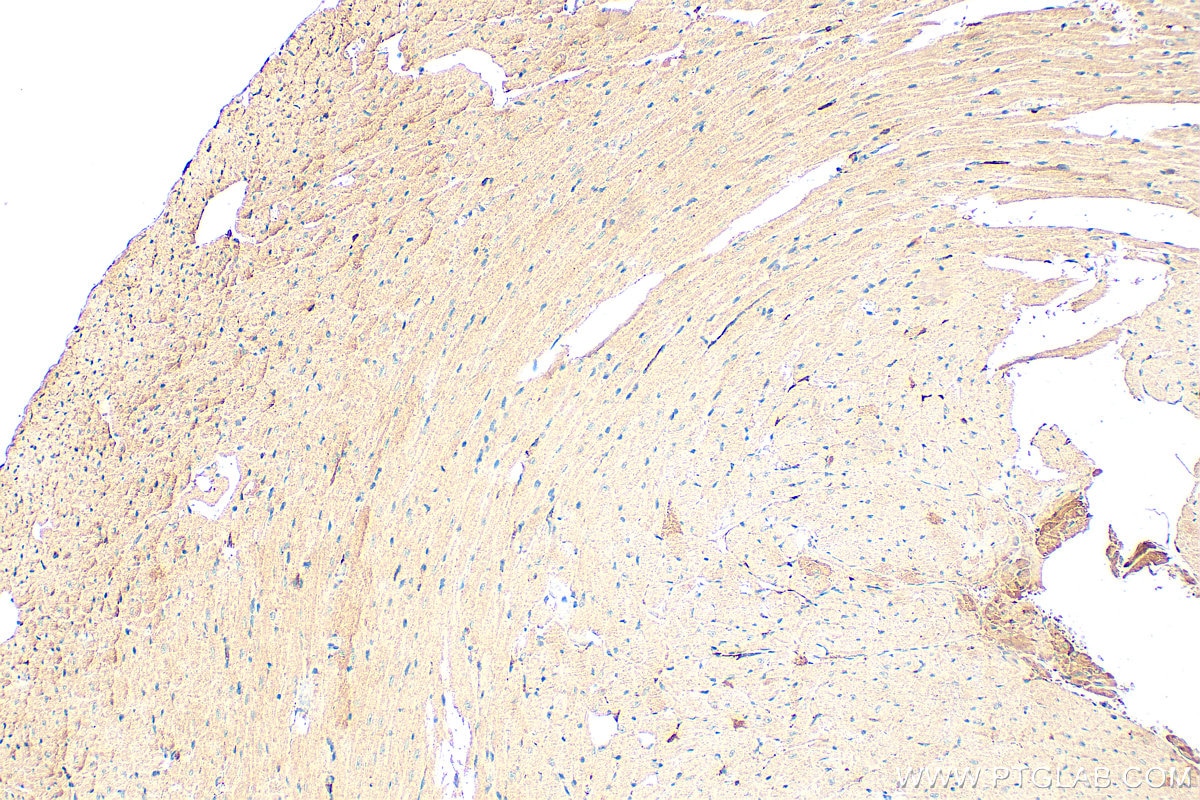

| Positive IHC detected in | human kidney tissue, mouse heart tissue Note: suggested antigen retrieval with TE buffer pH 9.0; (*) Alternatively, antigen retrieval may be performed with citrate buffer pH 6.0 |

20467-1-AP targets Spexin in IHC, IF-P, ELISA applications and shows reactivity with human, mouse samples.